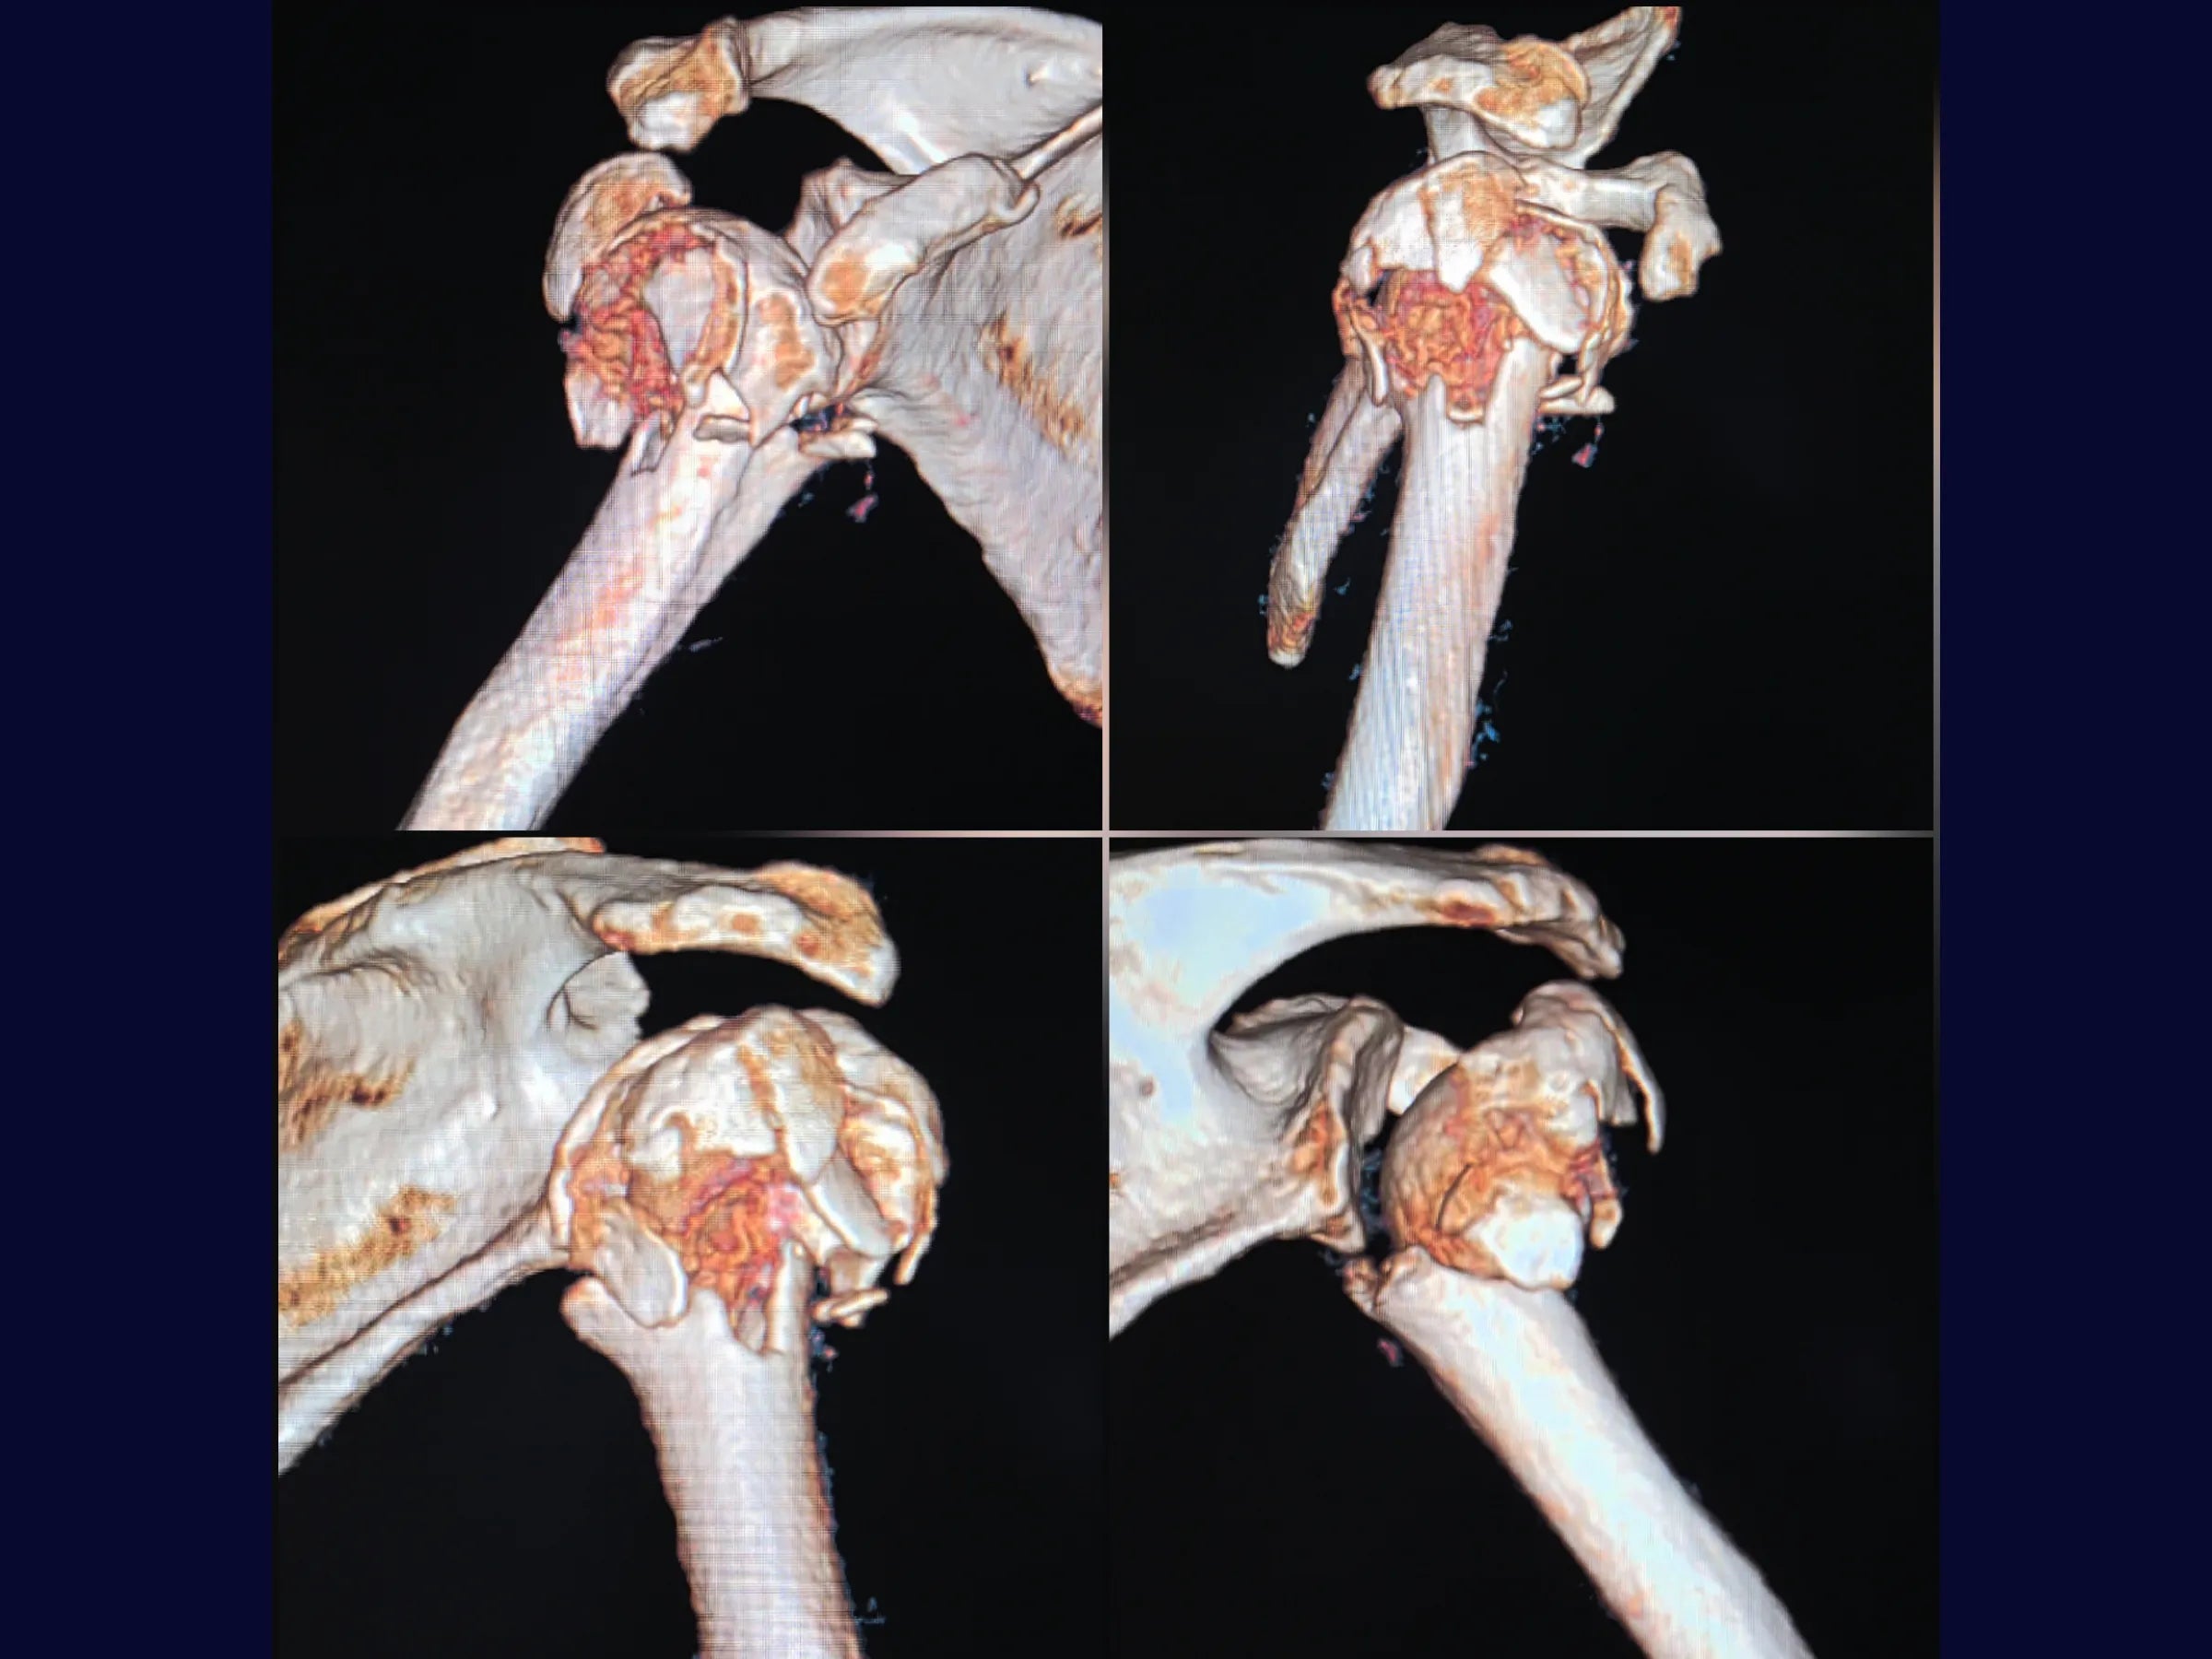

As fraturas complexas do úmero proximal, especialmente em quatro partes com impacto em valgo, exigem domínio técnico para restauração da anatomia e função.

- Abordagem deltopeitoral e identificação dos marcos anatômicos;

- Redução da cabeça umeral impactada em valgo;

- Redução anatômica das tuberosidades com tração controlada;

- Fixação com placa bloqueada e parafusos do calcar;